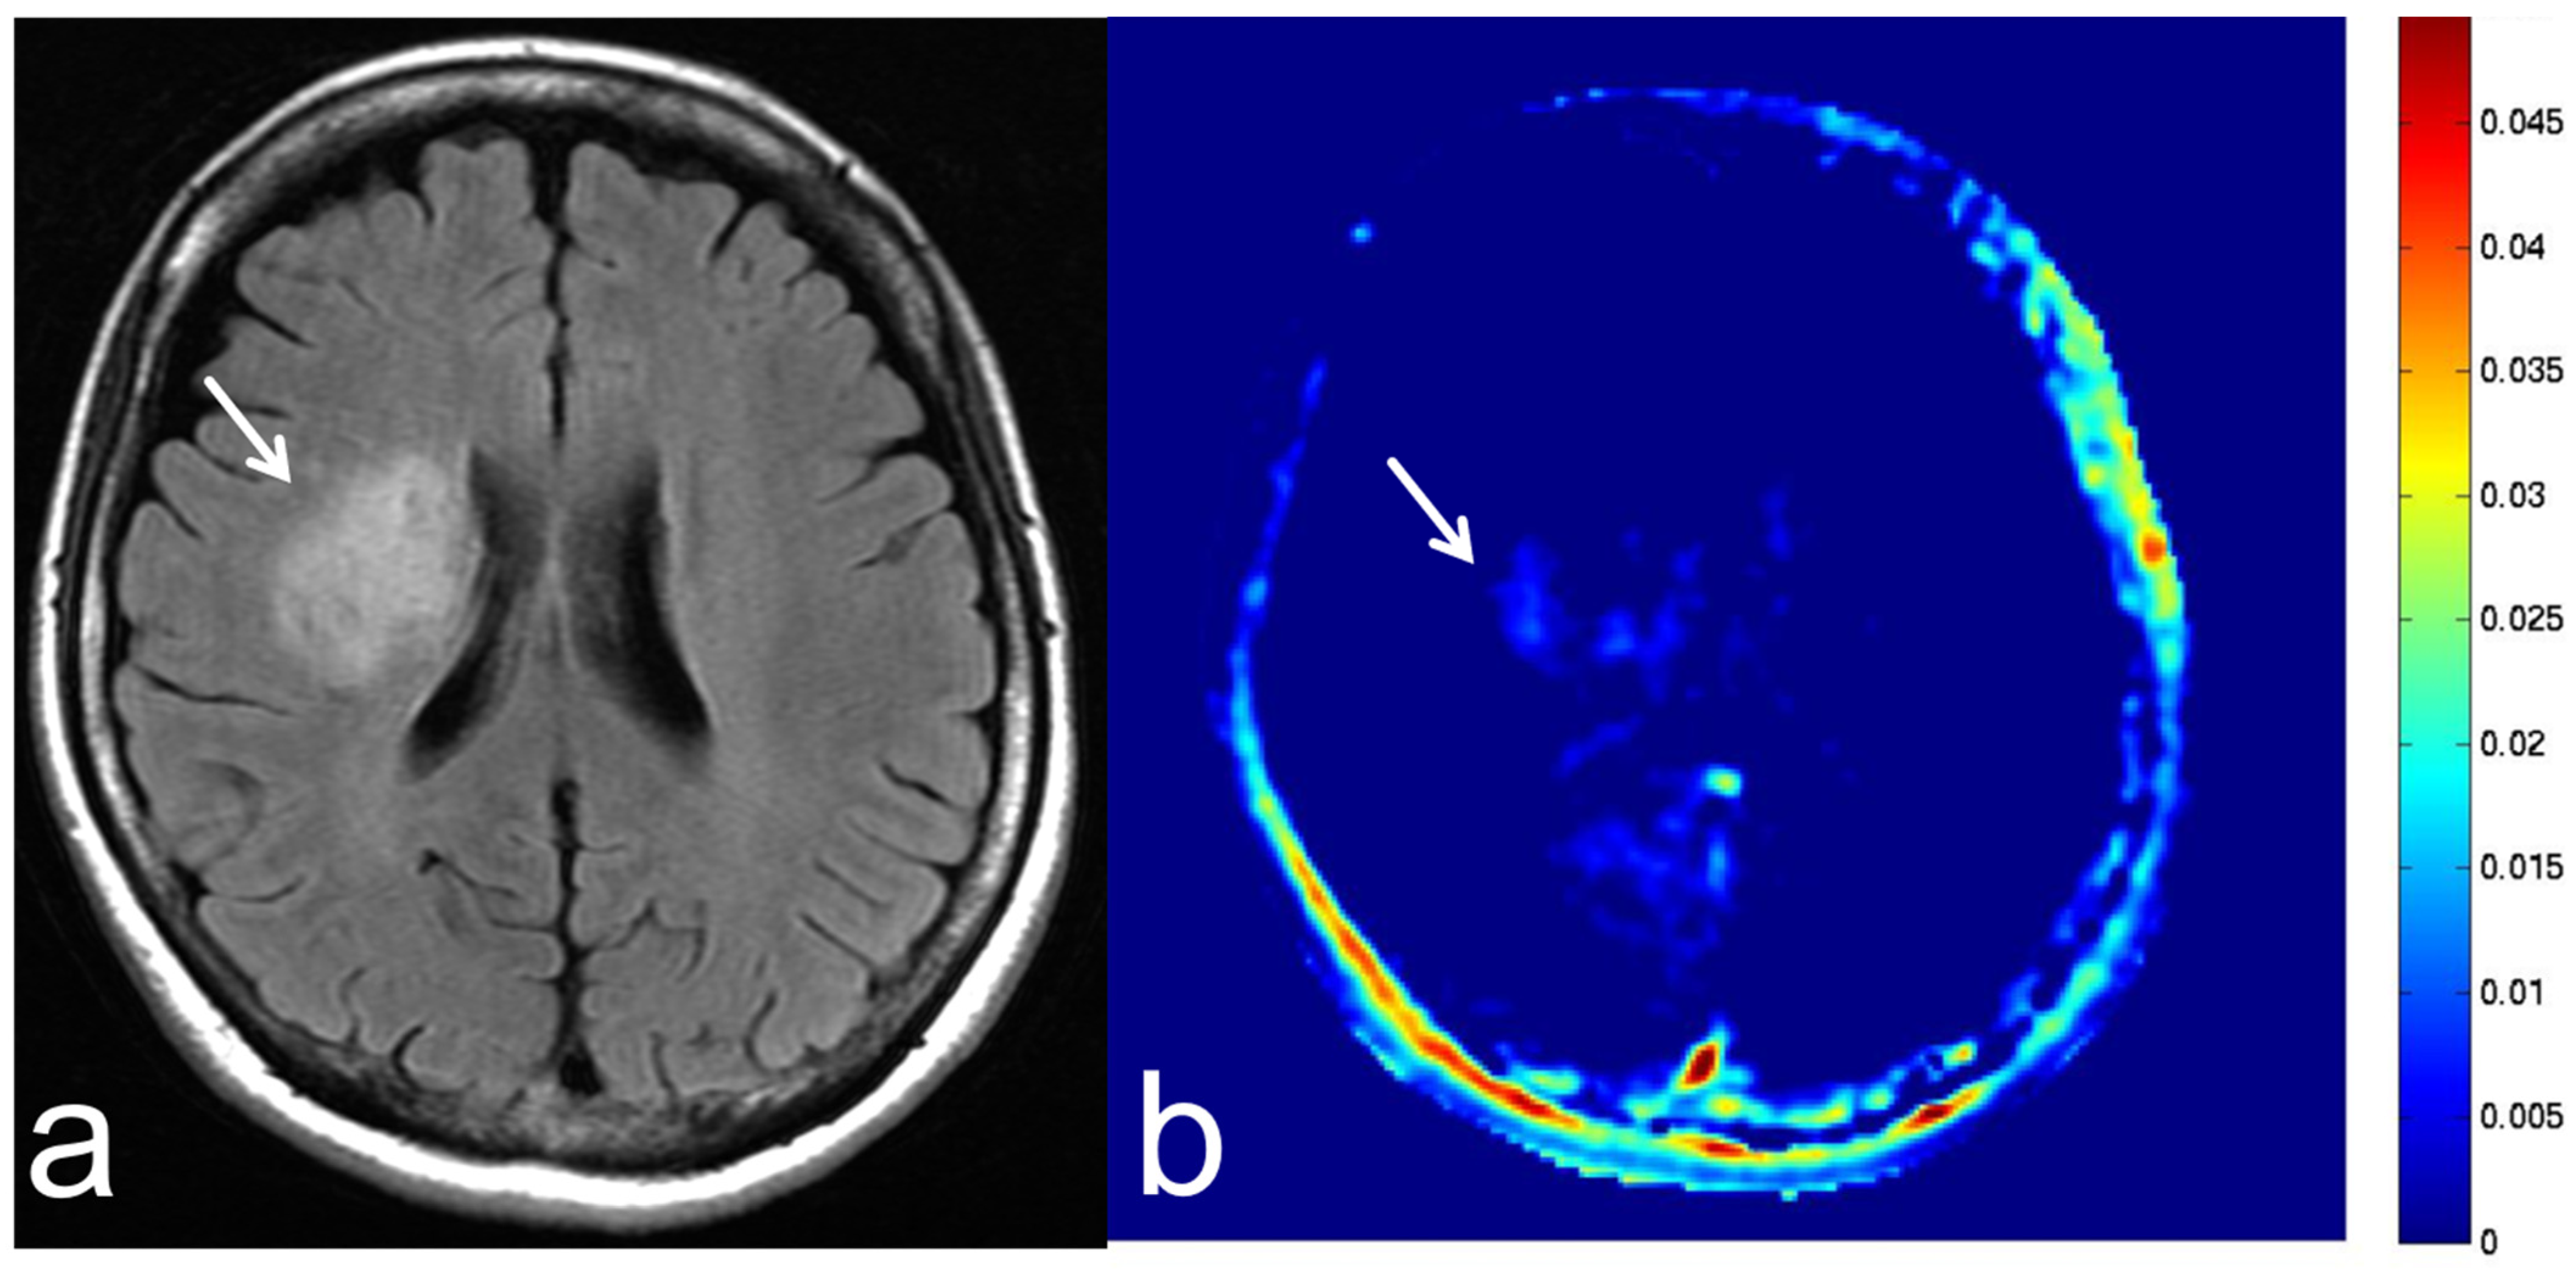

5.3. Glioblastoma